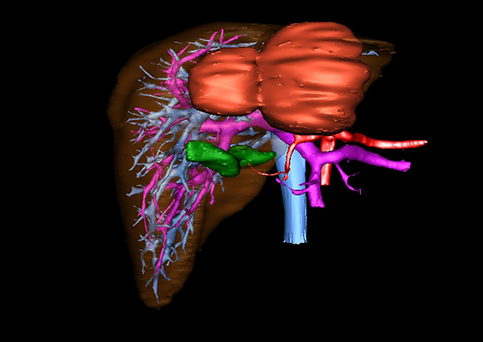

图1 位于肝右的叶肝母细胞瘤, 6个月,男婴

目前常用的检查方法有B超检查、CT、MRI、血管造影等。与其它的腹部肿块的诊断不同,对于小儿肝母细胞瘤血管造影具有重要的意义,可以作为手术前介入治疗的手段,也可为手术提供非常有效的影像学指导,但技术要求高,操作较复杂,且给患儿带来一定的痛苦。近年借助计算机辅助手术系统进行CT原始影像三维重建、手术规划和计算机虚拟手术技术,为精准肝脏手术提供了极为有效的技术支持。

近年来由于数字医学的发展,基于可视化三维重建技术的计算机辅助手术系统极大推进了小儿肝脏肿瘤的精准手术的进步。可以立体透视肝脏解剖、精确掌握肝段的边界、精确测算肝段乃至任意血管所支配的功能体积、准确定位病灶及其与邻近血管的解剖关系,最终对不同手术方案进行比较、筛选和优化。因此,计算机辅助手术规划系统是实现精准肝切除的有力辅助工具,是未来数字外科、精准外科等21世纪外科新理念的重要技术支撑。

计算机辅助手术规划系统具有良好的操作可行性、计算准确性和三维显示效果,可半透明、交互式显示真实的肝内立体解剖关系和空间管道变异,准确计算肝内管道的直径、走行角度,两点间的垂直距离,和任意血管的支配或引流范围等传统二维影像无法获取的信息,有助于实施个体化手术,提高了手术的确定性、预见性和可控性。计算机辅助手术规划系统可直观显示预留肝脏的结构和功能,并可通过虚拟切割功能辅助术者对手术方案进行蹄选和优化,系统评估手术风险和制定对策,改变了部分二维规划的术式和切除范围,使部分二维规划认为不能切除的患者成功手术,提高了手术的根治性、安全性和病变的可切除性,更加符合精准肝脏外科的术前规划要求。详见第11章。

随着计算机技术及影像检查技术的不断发展,以精确的术前影像学和功能评估、精细的手术操作为核心的精准肝切除技术日益受到重视。基于数字医学的计算机辅助手术技术(computer-assisted surgery,CAS)则是实现肝脏精准手术操作的基础。计算机辅助手术系统(CAS)可将术前二维(two dimensional,2D)的CT/MRI影像数据进行三维(three dimensional,3D)重建,建立个体化的肝脏三维解剖模型,清晰显示肝脏内脉管系统的走行及解剖关系,还原病灶与其周围脉管结构的立体解剖构象,准确地对病变进行定位、定性和评估,制定合理、定量的手术方案,实施个体化的肝脏血管取舍分配方案及实施精准肝脏手术。一般认为CAS包括:创建虚拟的患者的图像;患者图像的分析与深度处理;诊断、手术前规划、手术步骤的模拟;术中实时导航。应用本技术后,由于可以更清晰地看出肿瘤的界限,特别是根据肝血管的显影,判断出肿瘤与门静脉及肝静脉的关系以在手术前较准确地估计出手术成功切除的可行性。以往部分根据普通强化CT判断无法手术的病例而被评估为可以成功切除并手术成功。